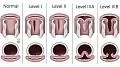

- Классификации